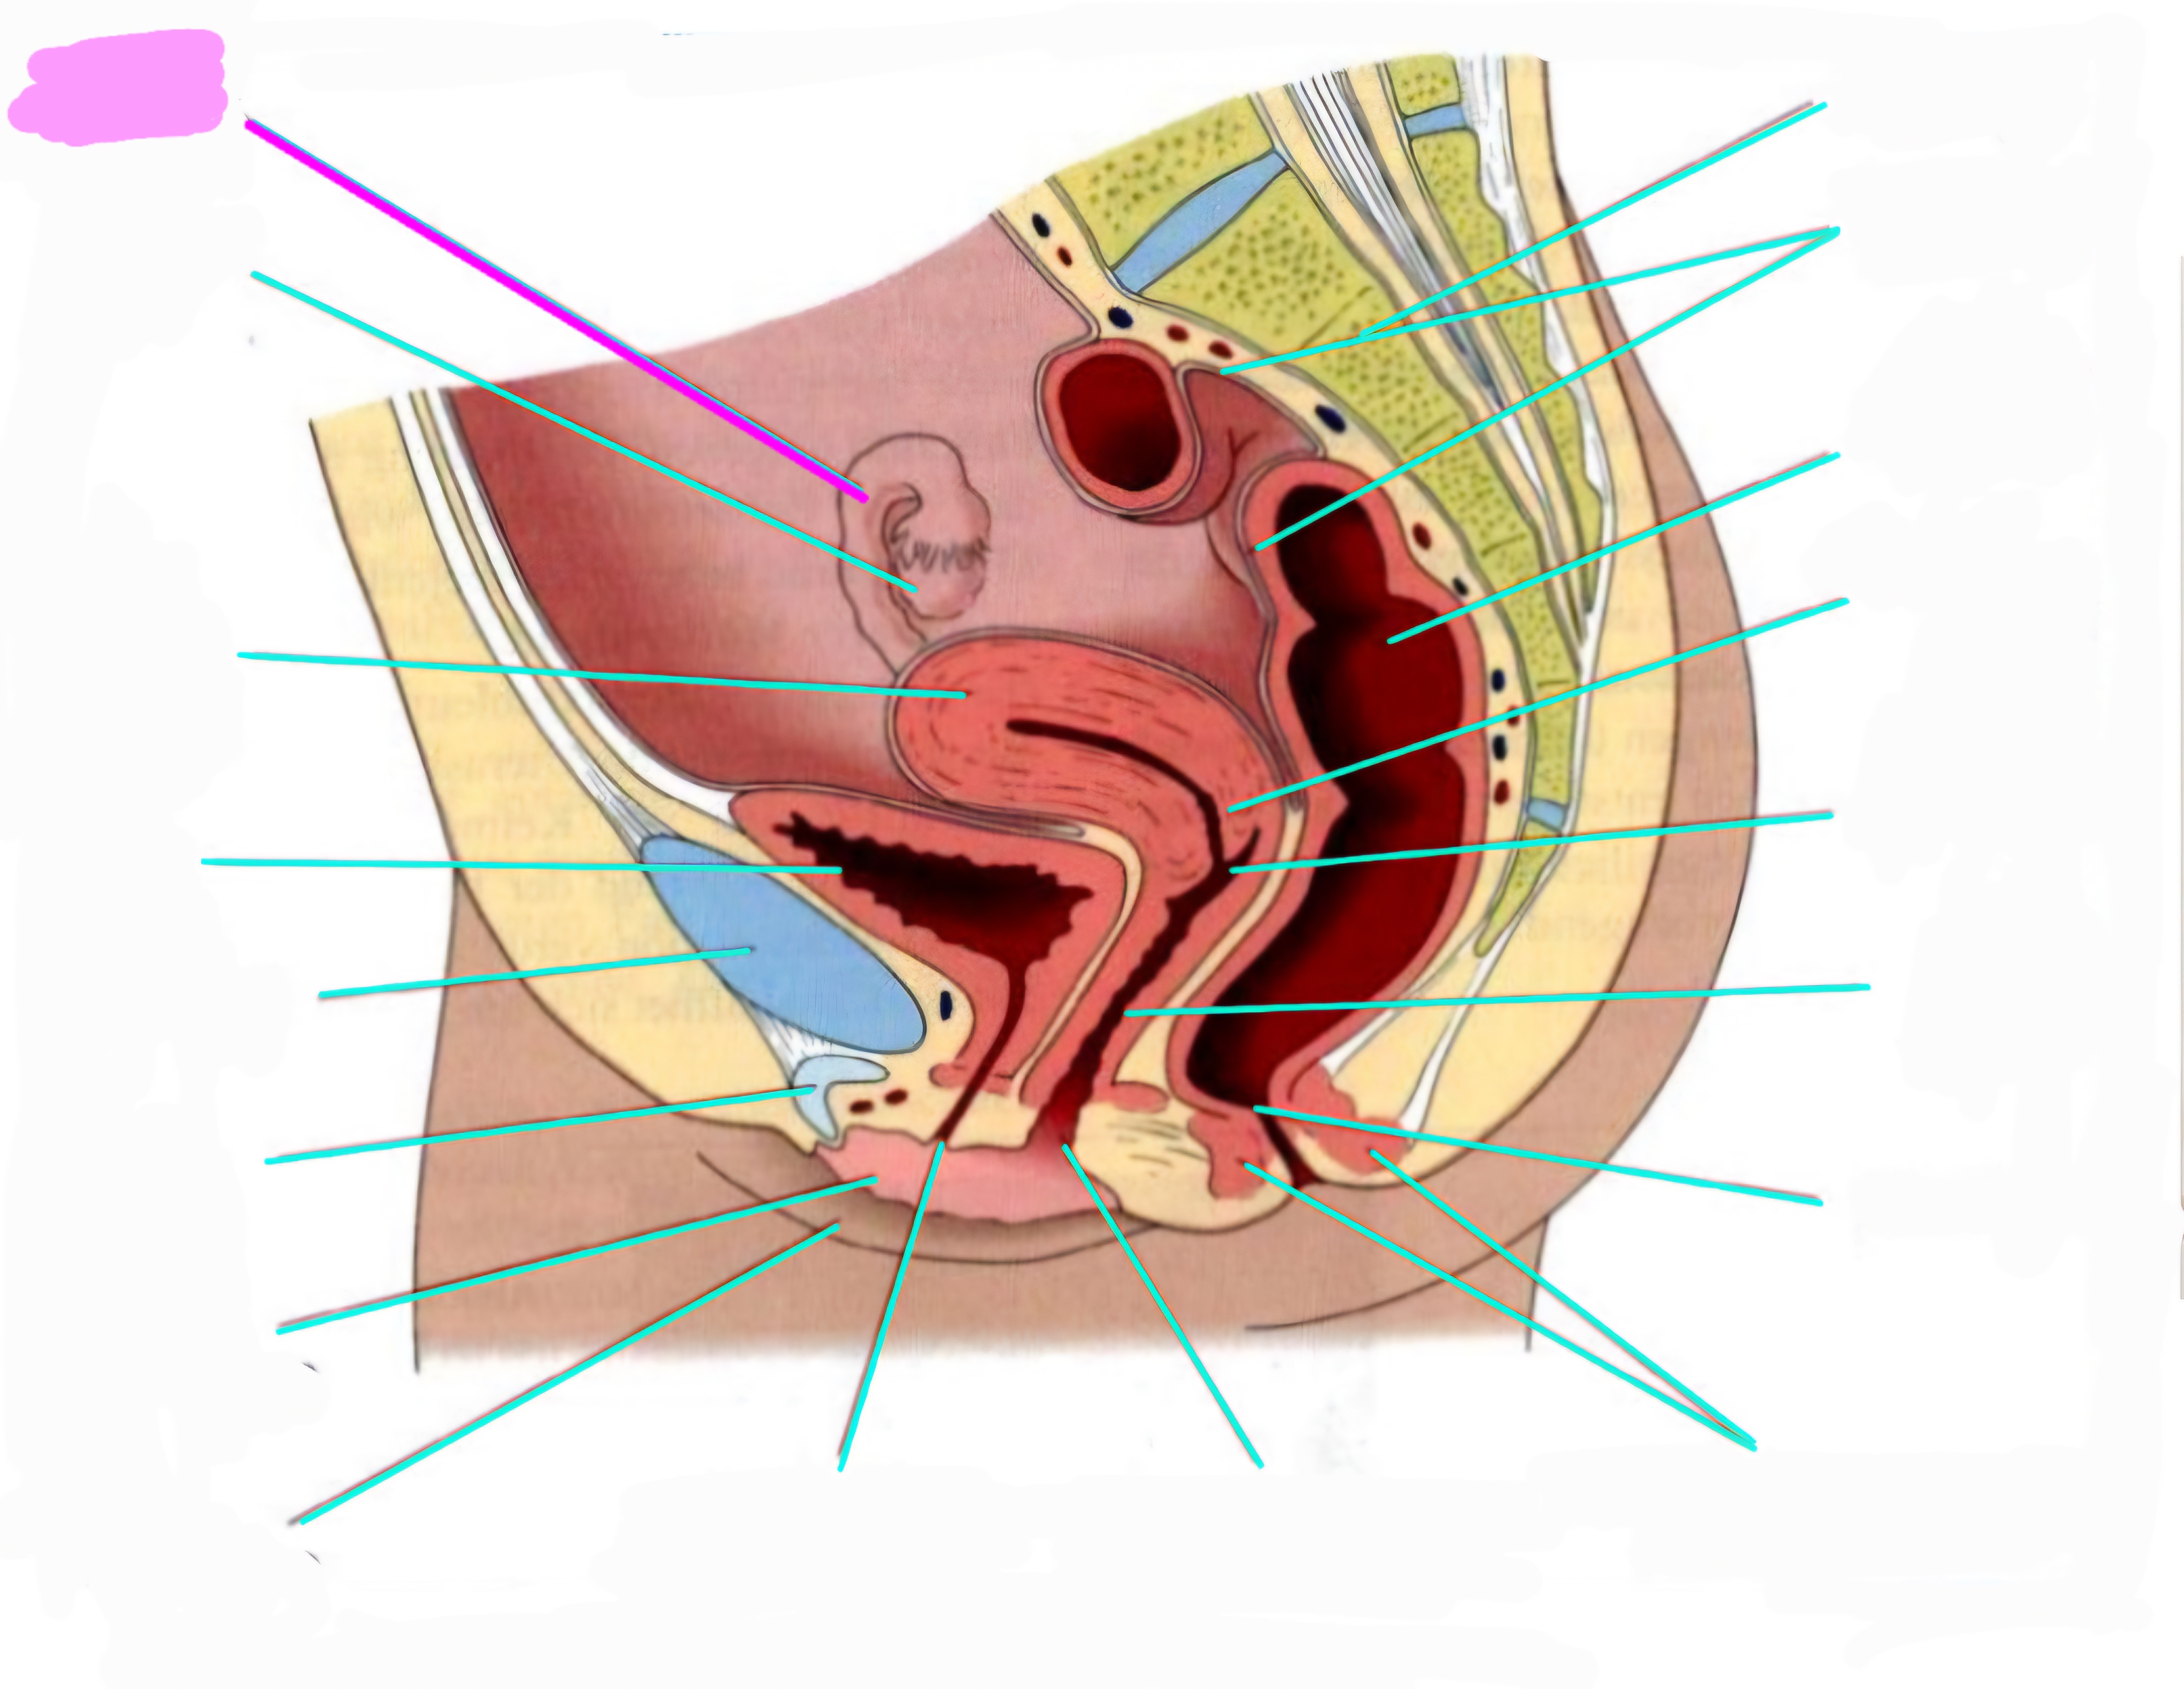

wbl. genital Anatomie

19 Terms

Tubea uterina (Eileiter)

Ovar (Eierstock)

Uterus (Gebärmutter)

Vesica Urinaria (Harnblase)

Symphyse

Klitoris

Labia minor pudendi (kleine schamlippen)

Labia Majoran pudendi (große Schamlippe)

Urethra (Harnröhre)

Introitus vaginae (Scheideneingang)

Sphincter ani externes (äußere Afterschließmuskel)

Anus (After)

Vagina (Scheide)

Portio (äußerer Muttermund)

Rektum (Mastdarm)

Zervix (Gebärmutterhals)

Peritoneum (Bauchfell)

Os sacrum (Kreuzbein)